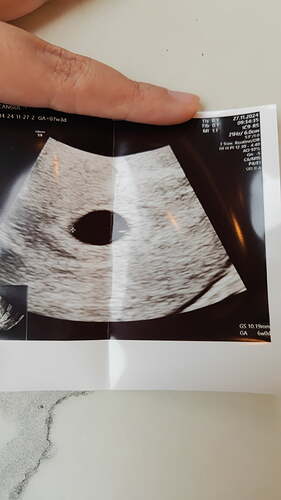

4 hafta iki günlük dü

Siz şanslıymışsınız ne güzel 4 haftalıkken görmüşsünüz bebeğinizi ![]()